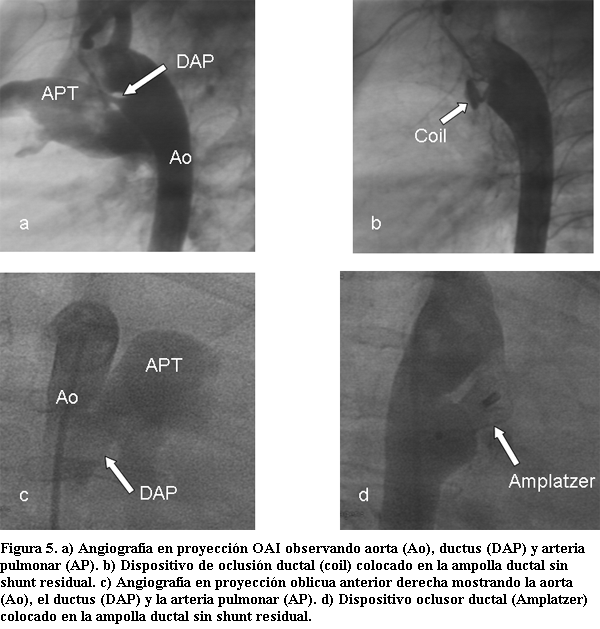

Cierre del ductus arterioso permeable

Desde los trabajos de Porstmann en los años 70 (30) se inició la era del cierre del ductus mediante dispositivo implantado por cateterismo, y al igual que lo que ha ocurrido con la CIA, muchos dispositivos se han diseñado, siendo pocos los que han demostrado una ecuación riesgo-beneficio inclinada a favor del paciente. El hallazgo de un ductus en un paciente virgen de tratamiento o residual a un intento de cierre previo, obliga a realizar su cierre para evitar la evolución a la insuficiencia cardíaca, la enfermedad vascular obstructiva (síndrome de Eisenmenger) o a una endocarditis infecciosa. En el momento actual la vía de elección para el cierre es la percutánea (a excepción del ductus del prematuro). Los dispositivos existentes son: para ductus de pequeño tamaño los coils de Gianturco o los Flipper coils (dispositivos de forma espiralada con un núcleo central de acero inoxidable rodeado de fibras de poliéster que aumentan su trombogenicidad, de liberación no autocontrolada y autocontrolada, sea por un sistema de sujeción de bolita o de rosca) y para los ductus de mayor tamaño los dispositivos Amplatzer PDA (formados por una malla de nitinol tubular, un disco aórtico de retención y un parche central de poliéster); hay otros dispositivos como el Nit Occlud pfm aún no autorizado en nuestro medio (31). Se efectúa el procedimiento bajo anestesia general, monitorización no invasiva de presión arterial sistémica, electrocardiograma y oximetría de pulso. Las vías a utilizar para el cierre son la venosa y la arterial retrógrada, el uso de una de ellas o ambas dependerá del tipo y tamaño del ductus y del dispositivo a utilizar. Se realiza medida de presiones sistémicas y pulmonares con cálculo de cortocircuito, resistencias pulmonares y angiografía del cayado aórtico en cada paciente para definir tamaño y características anatómicas del ductus. Si bien el ecocardiograma confirma el diagnóstico, la anatomía exacta la tendremos con la angiografía aórtica (clasificación de Krichenko) para poder seleccionar el tipo y tamaño del dispositivo a emplear (32).

Con el uso de coils es habitual la presencia de shunt residual inmediatamente al procedimiento en un 20%-40% (que puede persistir días o semanas e ir al cierre espontáneo) pudiendo requerir del implante de más de un coil, con un éxito de cierre alejado mayor al 90%. Con el dispositivo Amplatzer se produce el cierre total en más del 98% de los casos (luego de un período inicial de unas horas de persistencia de shunt, sobre todo en los ductus de mayor calibre).

La complicación mayor es la embolización del dispositivo hacia la aorta o hacia la arteria pulmonar (en menos del 5%), obligando a la extracción de los mismos mediante catéteres extractores, en general sin necesidad de un procedimiento quirúrgico; menos frecuentemente (menos del 1%) se ha descrito la presencia de hemólisis vinculada a la presencia de shunt residual (tabla 4) (figura 5) (33-45).